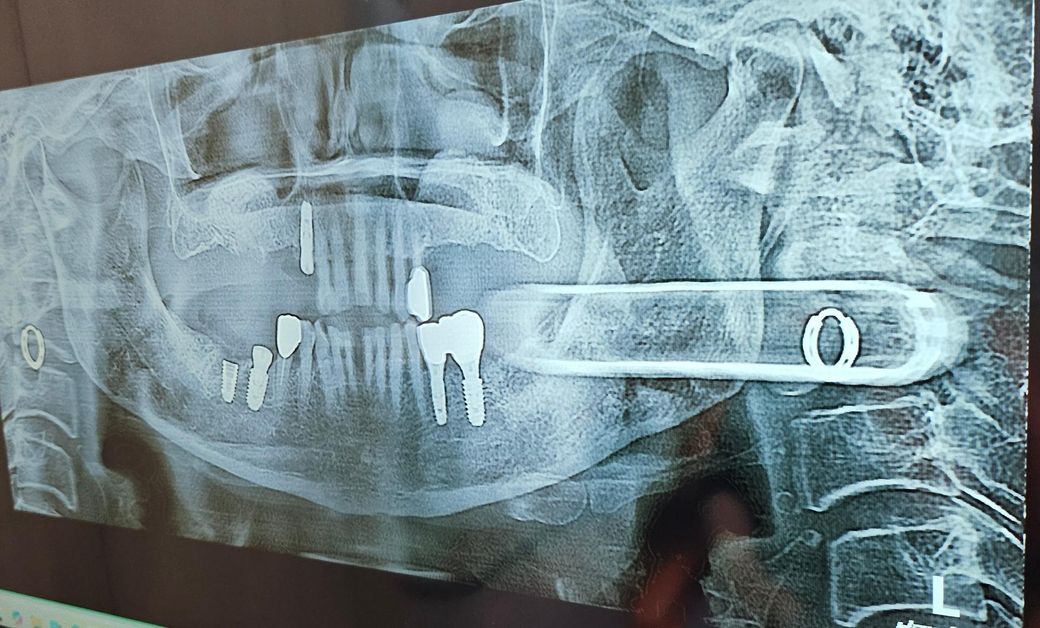

임플란트 틀니 임시치아 치료 어떻게할까요?

사진에서 임플란트 기둥 박은부분 크라운까지 한 상태이고, 위아래 치아 흔들리는치아가 몇개있어요

아래치아31,41많이 흔들려서 임시치아 부터 하고싶은데 임플란트 끝나고 난뒤하는게 나은지? 치아사이가벌어졌는데 발치는2개인데 크라운3개 하는게 맞나요?

• 1번 째 사진

현재 저 상태라면 10반대, 40번대(상하악 우측) 보철까지 마무리 하시고 상악은 부분틀니, 하악은 6번까지 어금니 있는채로 쓰세요

3. 추후 아래 앞니는 임플란트를 하거나 브릿지를 할때 크라운 형태를 2개로 할지 3개로 할지는 환자 선택입니다 2개로 하면 좀 비율이 안맞게 커질거고, 3개를 하면 정중선을 맞추지 못하고 다소 어색할 수 있습니다

일단 부분적으로 흔들리는 치아가 있고 양쪽 모두 임플란트를 하거나 치료를 하지 않고 부분적으로 치료를 진행하고 틀니를 하면 예후는 좋지 않습니다. 즉 전체적인 치료가 되어 있지 않아 부분적으로 계속해서 불편감이 나타나 결국에는 임플란트로 넘어갈 가능성이 큽니다.

아래쪽 치아는 이미 잇몸이 많이 내려간 상태이며 해당 치아를 크라운을 위한 임시 치아 자체는 의미가 없으며 발치 이후 주변 치아로 브릿지를 하거나 임플란트를 해야 합니다.